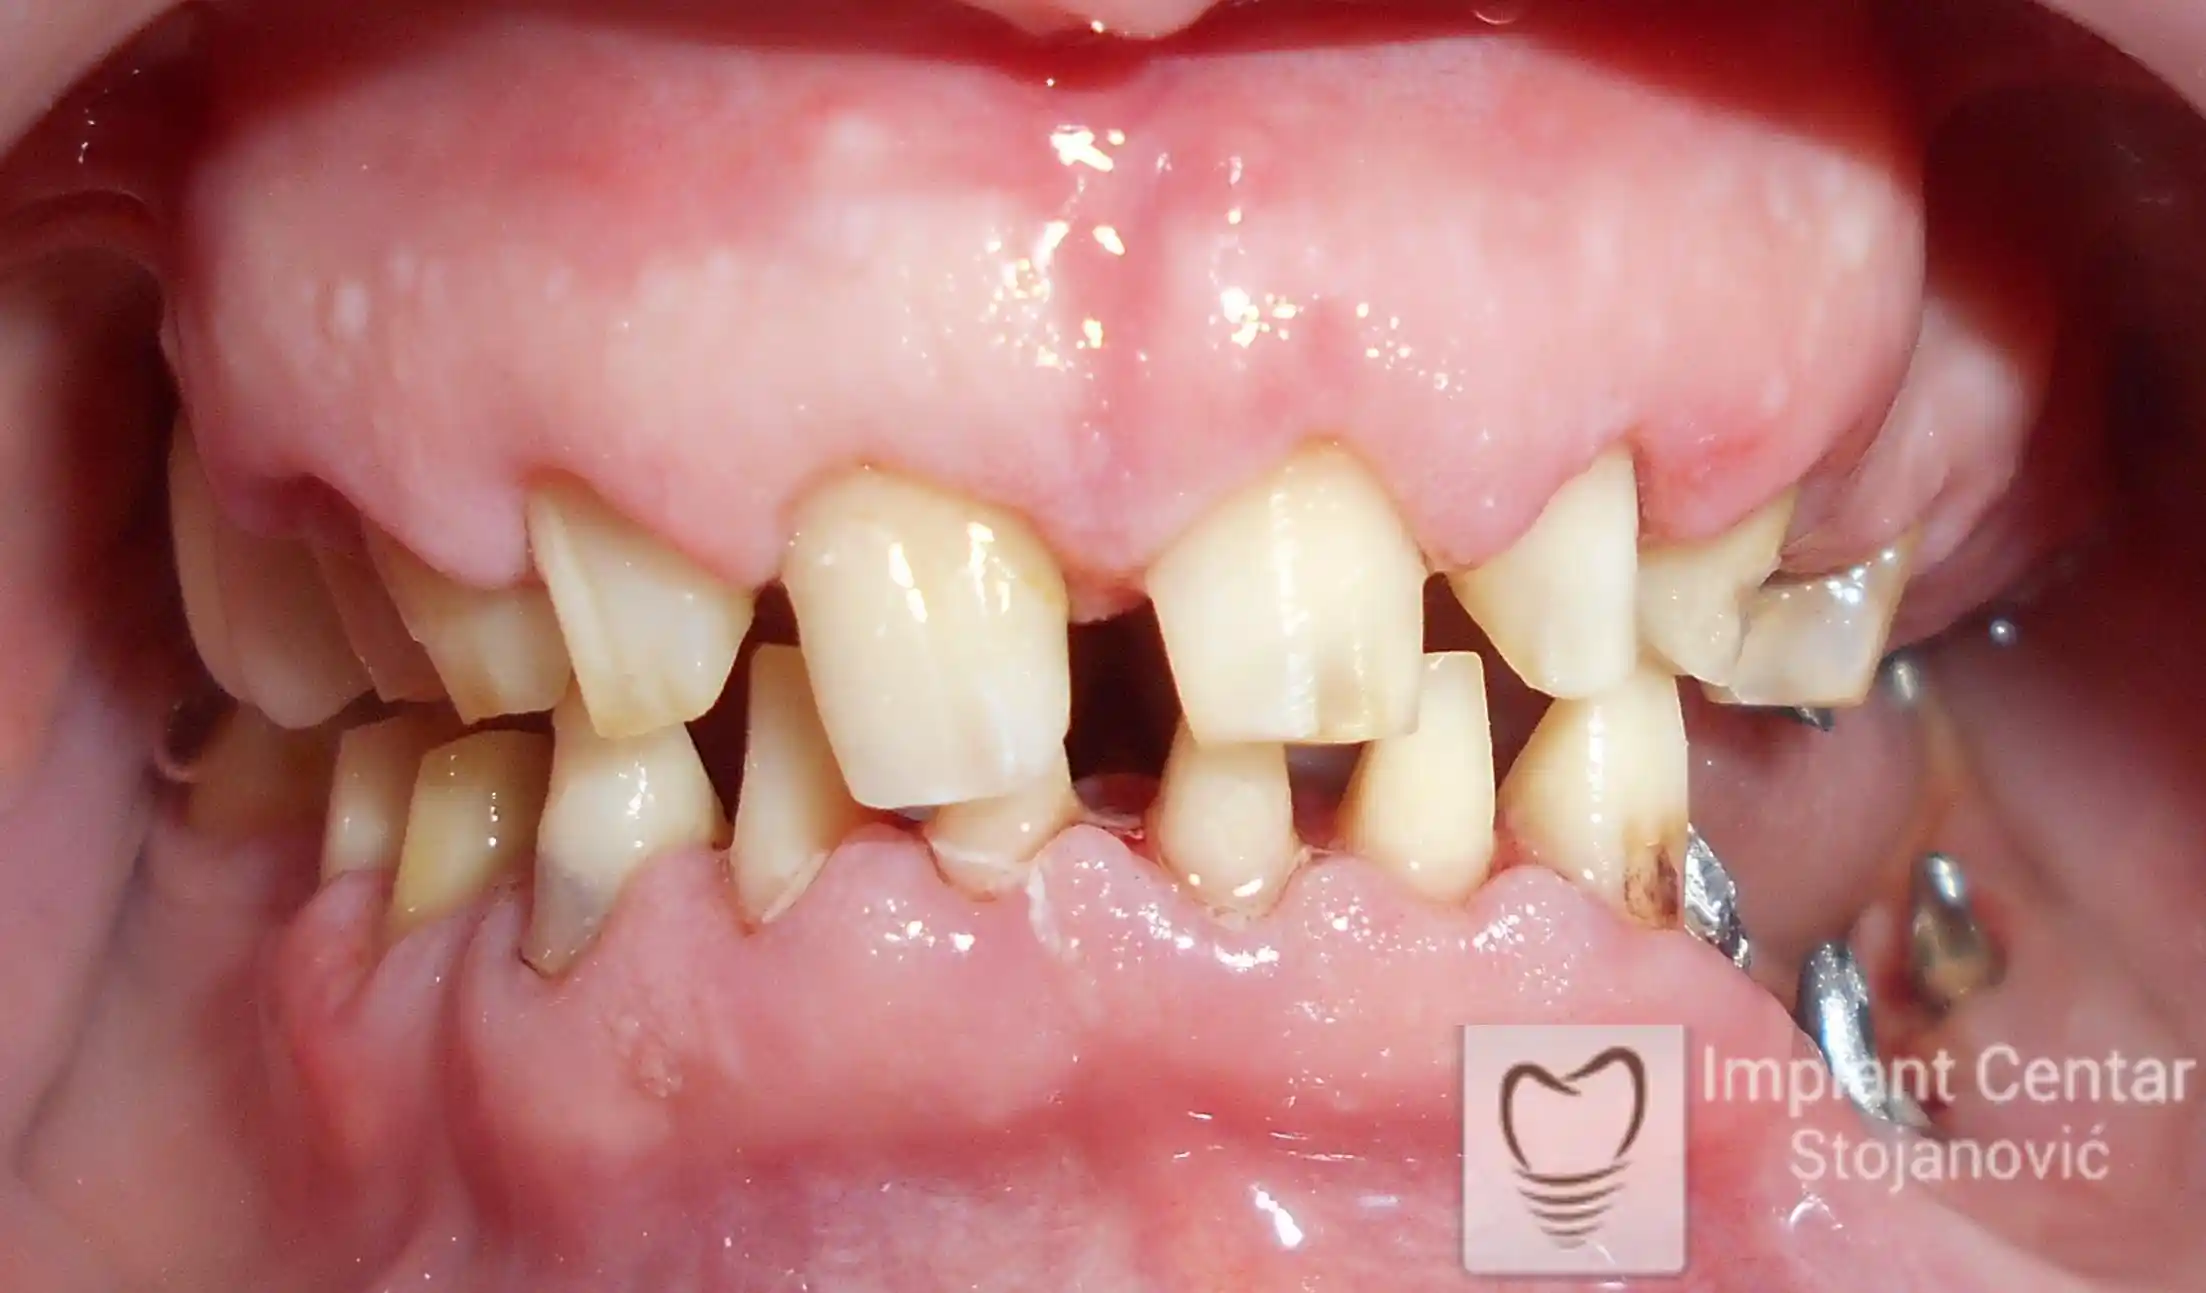

Na slikama 1, 2, 3 , 4  i  5 prikazan je izgled pacijenta pre početka terapije. Nakon detaljne kliničke i radiološke analize, doneta je odluka o vađenju zuba loše biološke vrednosti, dok su bezuba polja sanirana ugradnjom dentalnih implantata.

Na slici 1. slici 2. vidi se početno stanje — pacijent je imao prirodne zube, ali samo izradom novih mostova nije bilo moguće postići normalan odnos gornjih i donjih zuba (eugnatan zagrižaj).